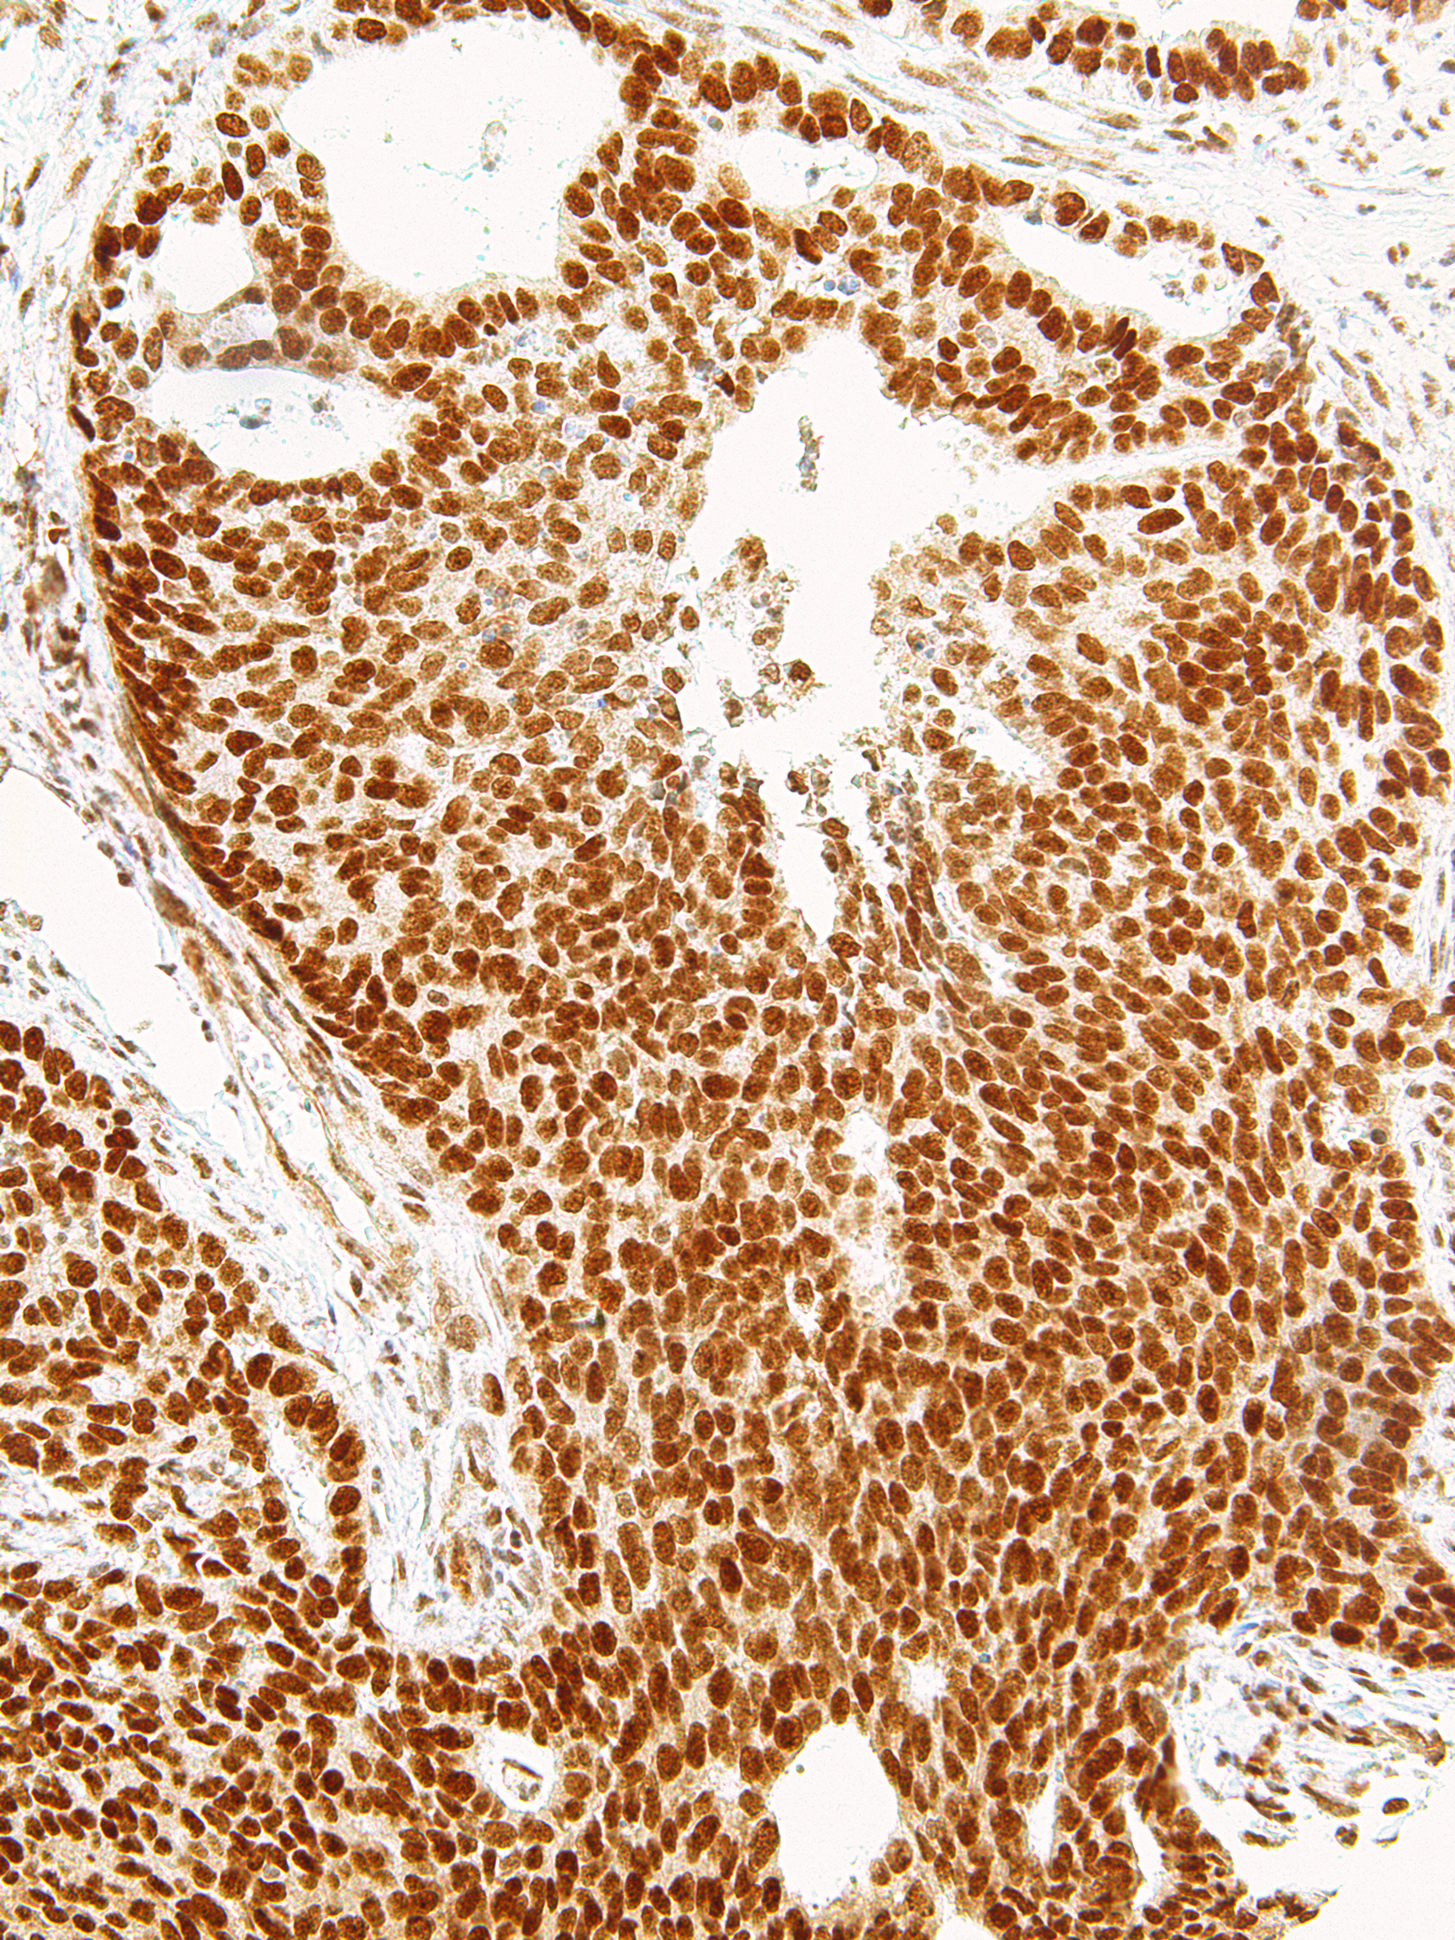

[Genomeme] EZH2

CAT. NO. IHC570-7

IHC570

IgG1

Mouse

Monoclonal

Prostate Adenocarcinoma, Tonsil, Breast Carcinoma

Enhancer of Zeste Homolog 2 (EZH2) is a methylase of histone H3 that silences gene expression in those regions. EZH2 is overexpressed or mutated in gastric, prostate, uterine, breast, and renal cell cancers, as well as in melanoma and most B- and T-cell lymphomas. Although EZH2 is usually present in follicular centers, it is not expressed in the mantle zones, plasma cells, follicular or interfollicular T-lymphocytes, natural killer T-lymphocytes, plasmacytoma, lymphoplasmacytic lymphoma, or MALT lymphoma. EZH2 is rarely present in normal breast duct epithelium and in normal and hyperplastic lymph node. Anti-EZH2 is also useful for detecting lymphoma and non-small cell lung cancers. EZH2 is associated with tumour proliferation and can be used in staining panels to distinguish aggressive lymphomas from less aggressive lymphomas or normal cells.